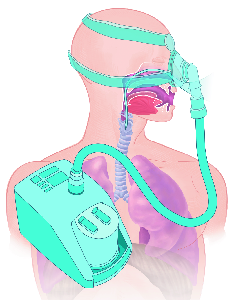

Detailreiche Fotografien aus der medizinischen Praxis ergänzen die Texte; moderne, genaue,

wissenschaftliche Zeichnungen geben Einblick in die Anatomie und die Funktion der Lunge und

anderer Organe.